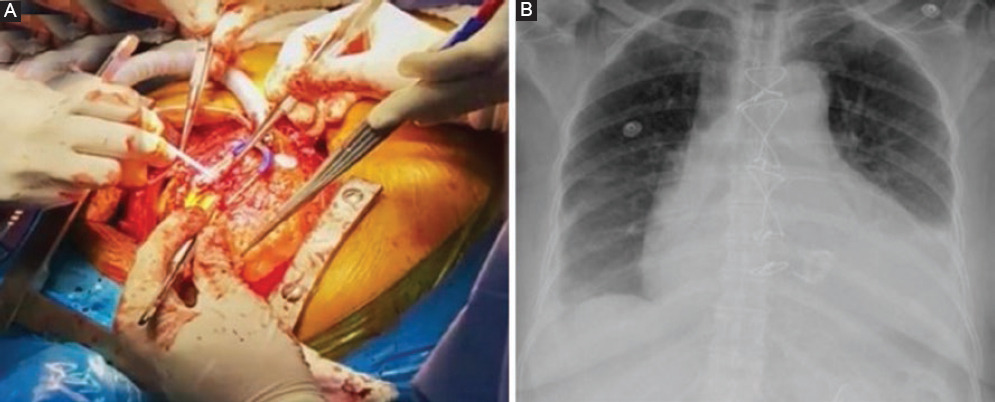

Por tratarse de sífilis cardiovascular se realizó tratamiento con penicilina benzatínica y al terminar la última dosis se procedió a la cirugía. La estrategia quirúrgica se discutió teniendo en cuenta los reportes de la tomografía computarizada, el ecocardiograma transtorácico y la angiografía coronaria. Se determinó enviar a la paciente para una sustitucion valvular aórtica por bioprótesis Perimount 21 más tubo supracoronario de 30 mm (Fig. 2 A y B). La biopsia del material resecado en la cirugía reportó valvulitis crónica cicatricial con extensas calcificaciones.

Figura 2 A: Intervención quirúrgica por esternotomía en la que se realiza corrección quirúrgica de sustitución valvular aórtica por bioprótesis Perimount 21 más tuvo supracoronario de 30 mm. B: Radiografía de tórax posquirúrgica.